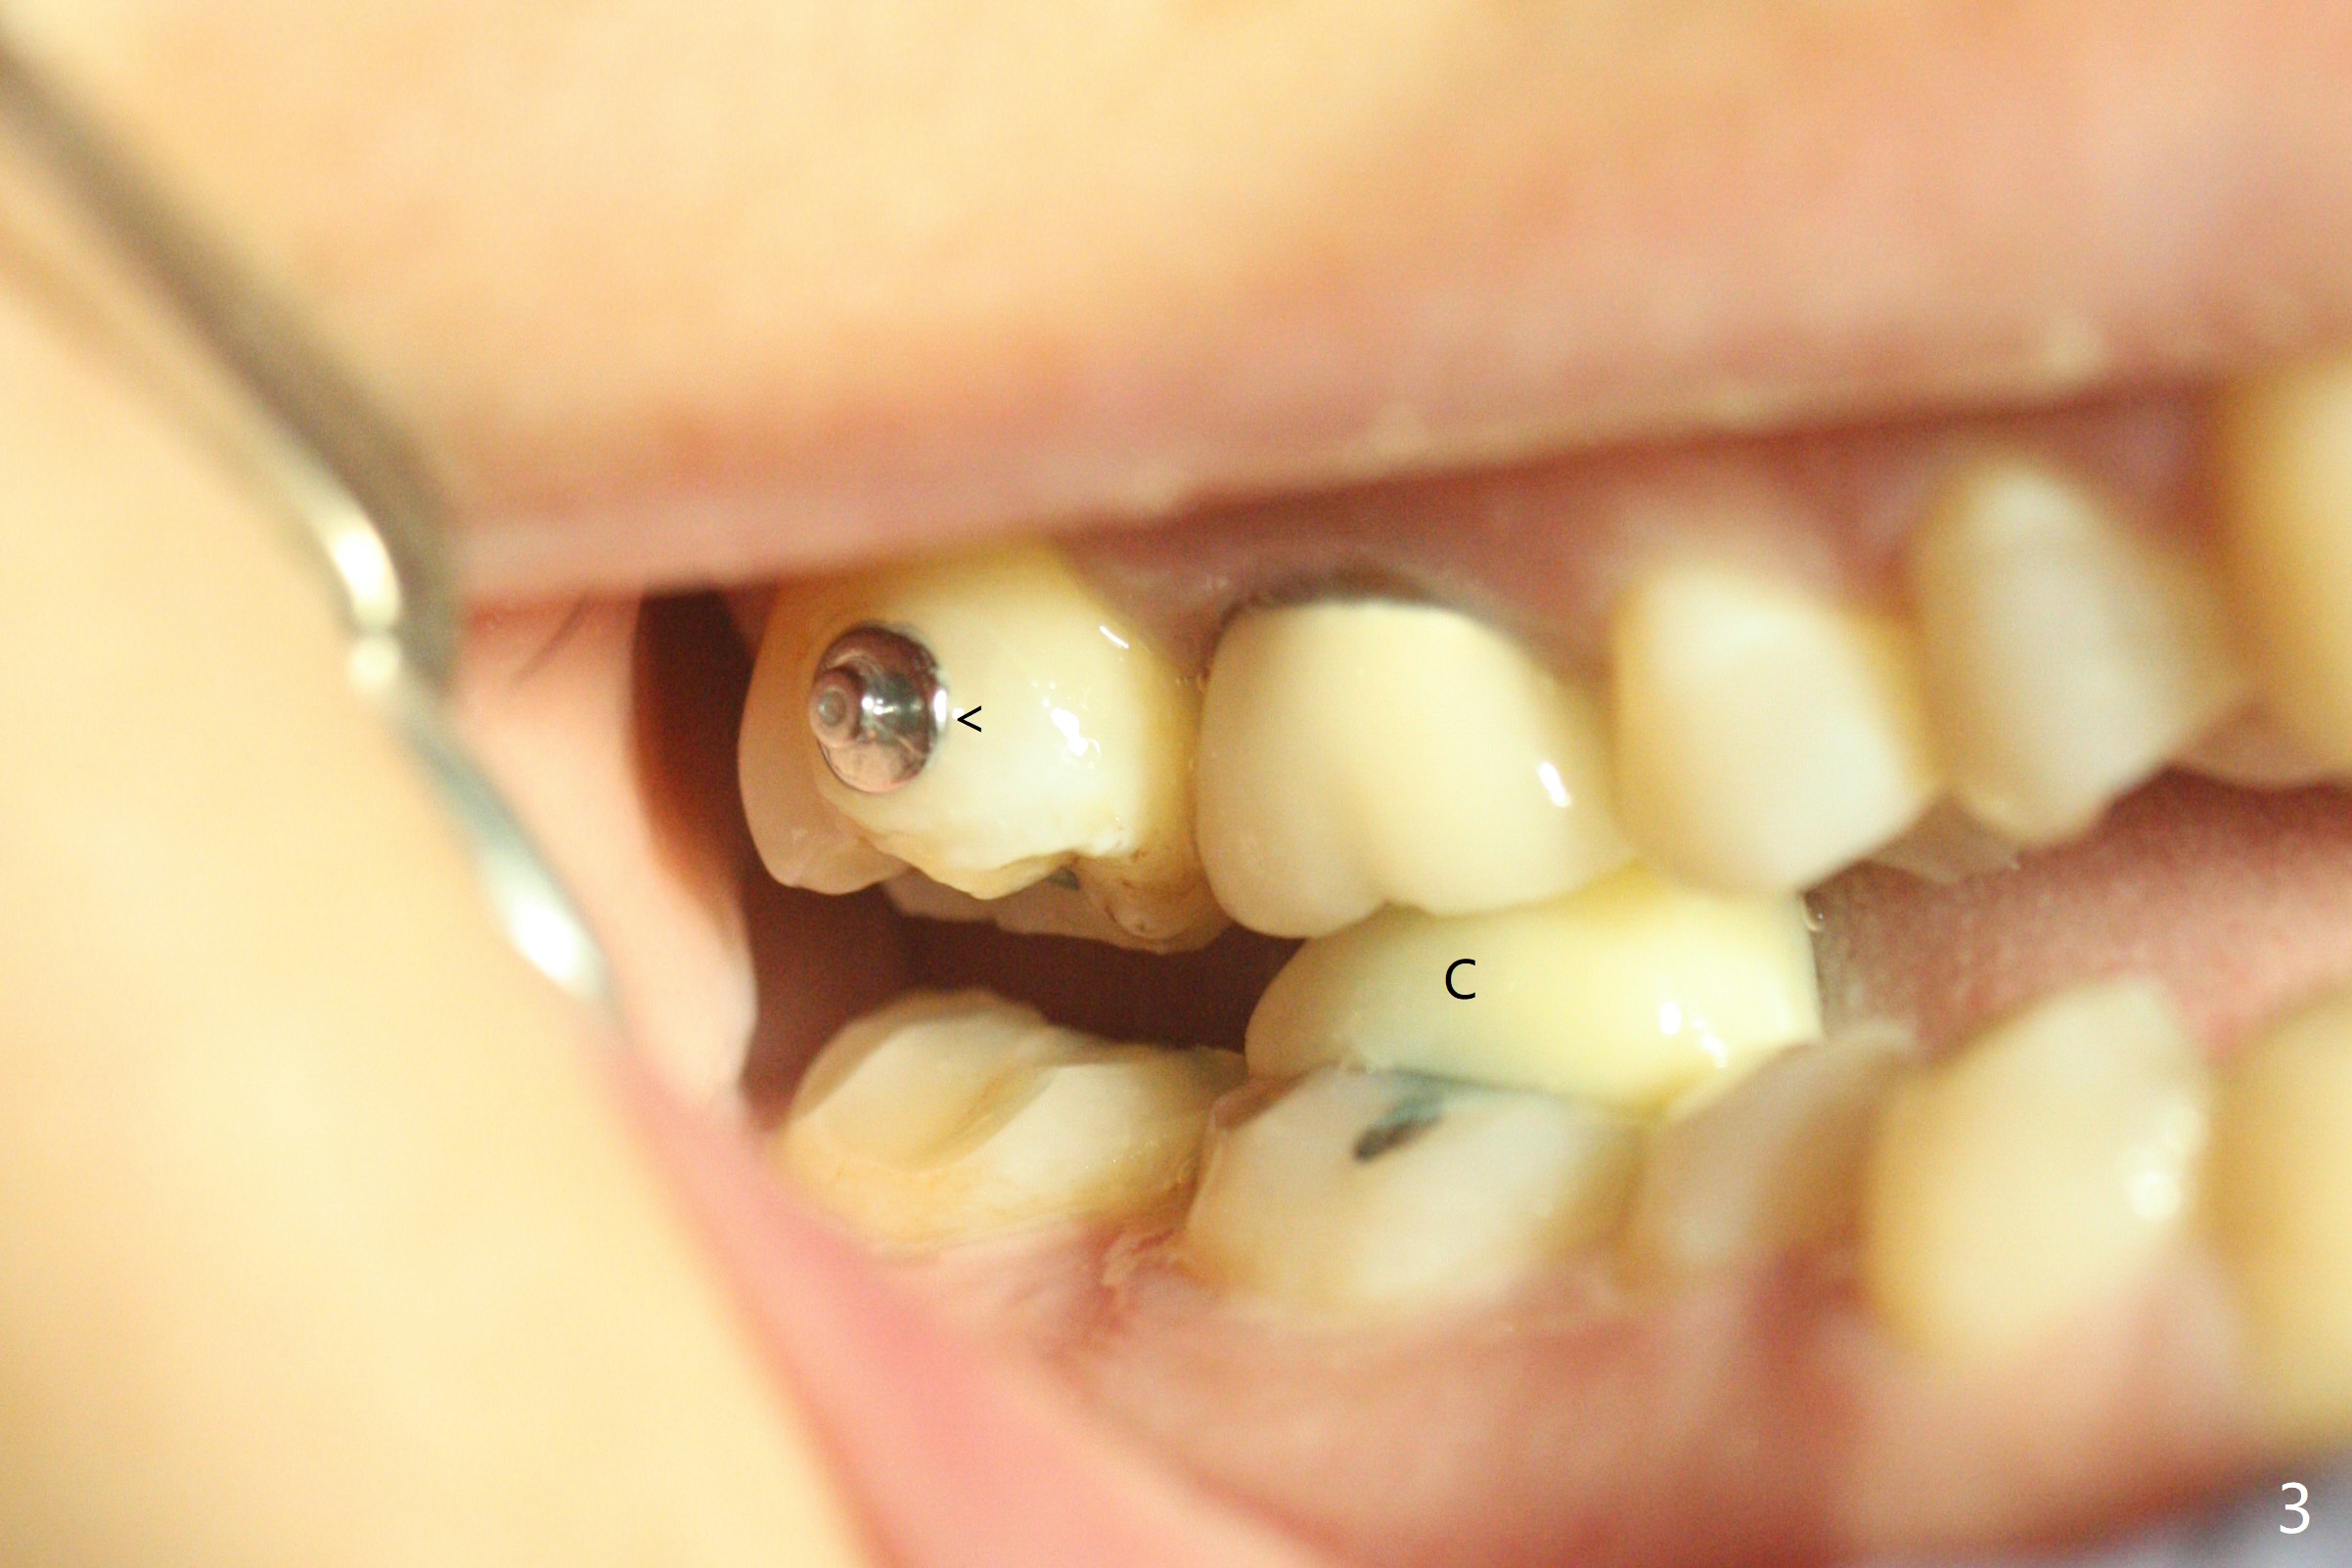

A 51-year-old woman agrees to correct cross bite of R7s 10 years post UR6 crown (Fig.1,2). Composite is placed in LR6 (Fig.3 C) and LL7 for clearance. Lingual buttons are placed in the buccal surface of UR7 (Fig.3 <) and lingual surface of LR7 (Fig.6 ^) with 6 oz. elastic in between. Cross bite correction finishes in 3 months. Photos (Fig.4-6) and PAs (Fig.7,8) are taken 11 days post orthodontic treatment.